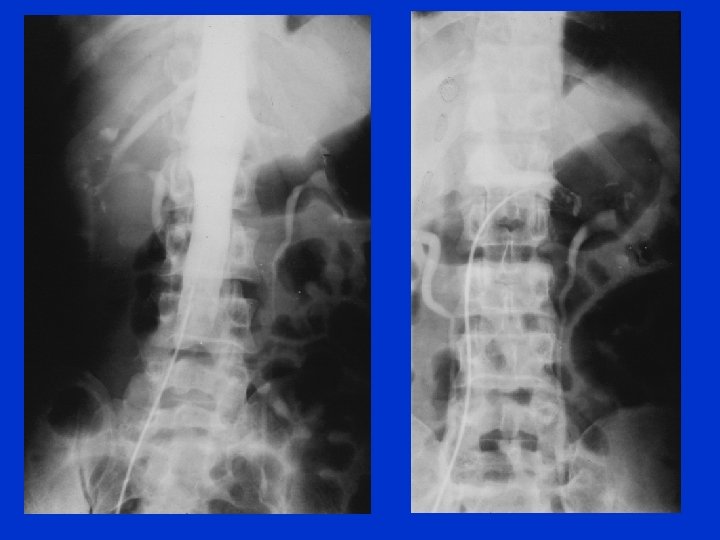

Mulher, 61 anos, com HA e DM tipo 2, há 2 dias apresenta dor lombar D, surda, associada a vômitos biliosos. Não apresenta edemas. Urina rotina: prot +++ e hemácias: 11 a 20/campo; Pcreat: 1, 0 mg%; colesterol total: 938 mg%; HDL: 44 mg%; TG: 811 mg%; Alb: <1, 0 g/d. L; PT: 3, 9 g/d. L; Upr: 8, 1 g/24 h; Biópsia renal: GN membranosa; Tratamento: heparina de baixo peso e warfarim na alta. N Engl J Med. 354(13): 1402, 2006.

Síndrome nefrótica e tromboembolismo • Incidência: – Adultos: 10% a 40% – Crianças: 2% a 4% • Veia renal: principal local de trombose